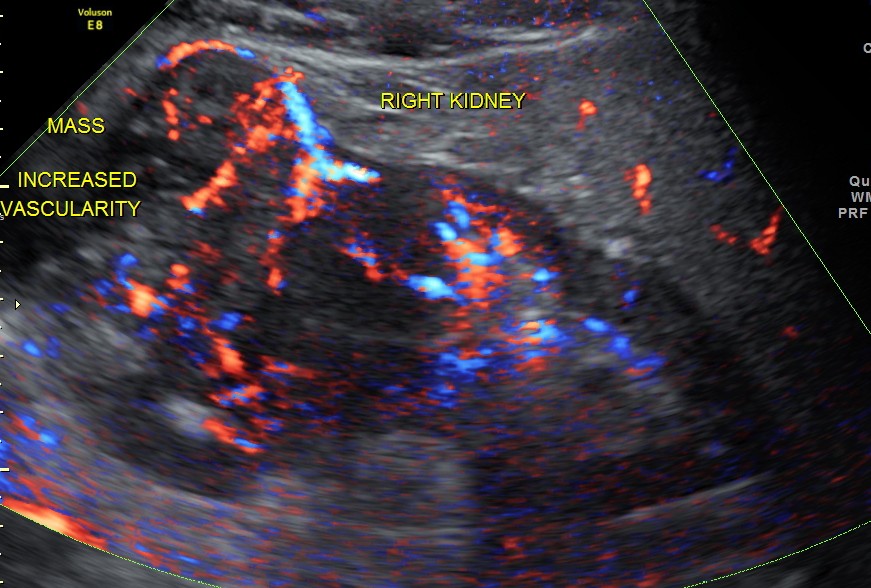

The right renal mass shows increased vascularity .

The images are presented to show the increased vascularity on colour Doppler and the lobularity seen in the reconstructed image and also for the clinical presentation of pain on the contralateral side due to herpes zoster.